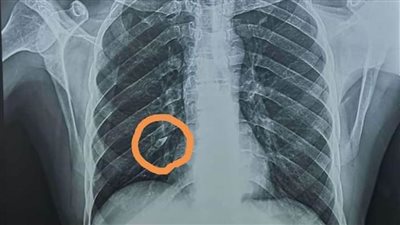

بنها الجامعى ينجح في استخراج "دبوس تنجيد" من صدر شاب